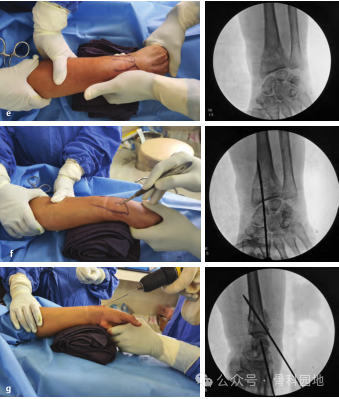

首先进行骨折闭合复位,牵引时须缓慢而持续,通过掌屈和尺偏来矫正背侧和桡侧移位。复位后,将手放在卷起的布单上,保持掌屈和尺偏(下图a,b),并用至少三根经皮克氏针固定。

第一枚克氏针在 Lister 结节进针,以 45°倾斜,瞄准桡骨长轴上近端骨块的掌侧皮层。如果进针点位于Lister结节的尺侧,可能会损伤拇伸肌腱。

第二枚克氏针自桡骨茎突远端 0.5 cm 处进针,克氏针与桡骨轴成 60°角,穿透骨折近端尺侧皮质。

第三枚克氏针在距腕关节线远端0.5 cm处,固定月骨窝骨块,位于第四和第五伸肌室之间。克氏针以 45 °角固定到桡骨的掌侧,如下图a、b 所示。

使用经典经皮克氏针固定桡骨远端骨折,如下图a-e 。